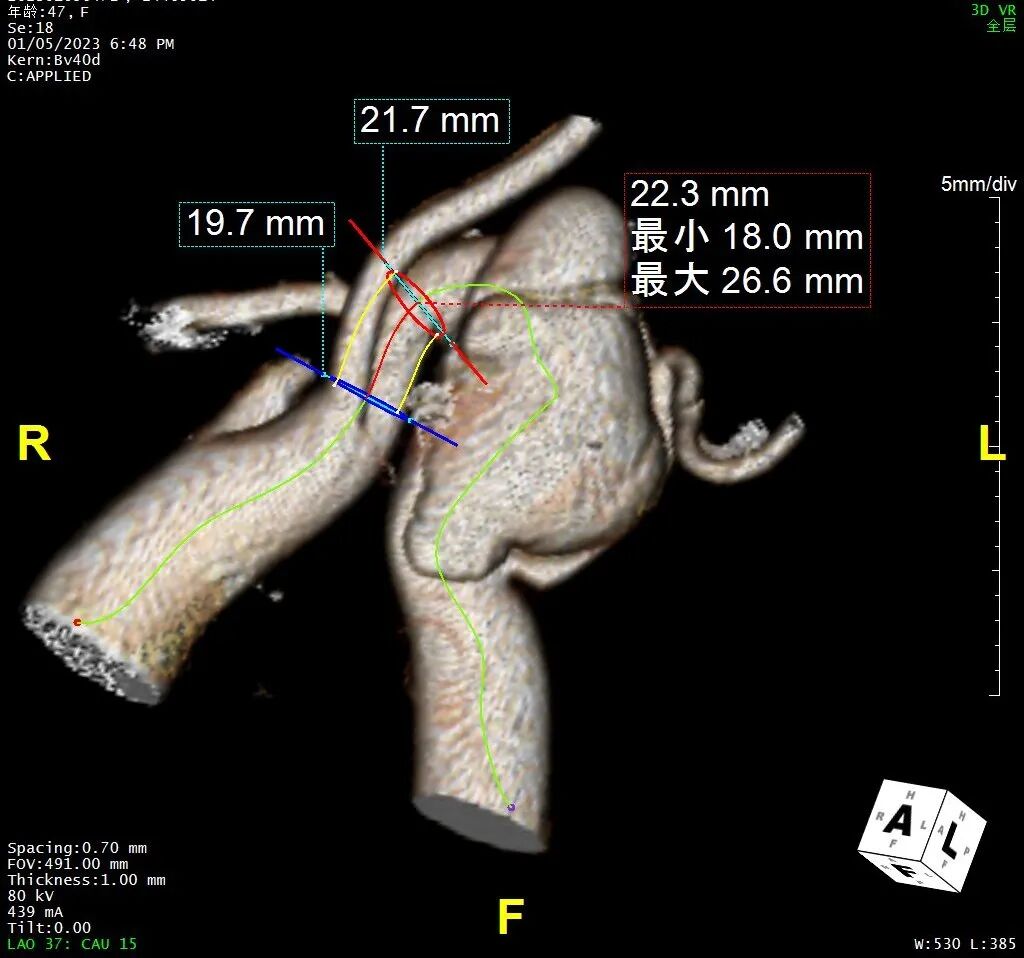

CTA检查

1、Ⅲ型弓,主动脉弓部远心端可见夹层动脉瘤,瘤体44mm*79mm,左锁骨下动脉发自瘤体下方降主段,且萎缩狭窄。

2、右椎动脉绝对优势,左椎动脉萎缩狭窄。

手术难点二

如何最大程度保证支架在释放时不移位?

根据CT测量结果,预计锚定区位于LCCA后缘,瘤颈长度为22mm,弓部直径19-25mm。支架必须准确的锚定在LCCA后,如果释放时发生前跳,则会覆盖LCCA,受血管直径影响,重建LCCA的空间有限;如果发生后移,则会因锚定区不足产生I型内漏,补救成本巨大。